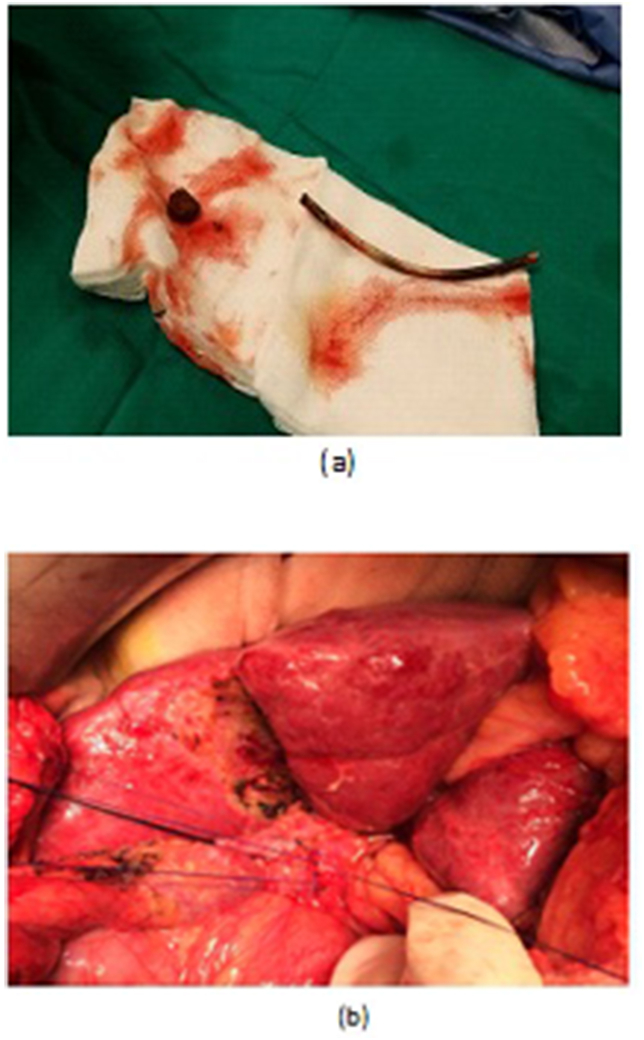

LCD: Under general anesthesia; we used the standard four-port technique of LC. Routine trans-cystic intra-operative cholangiography (IOC) was performed in all cases for identification of stones number, site and size. The gallbladder was left in situ for retraction until the operation was completed. When we reached CBD, a longitudinal supraduodenal choledochotomy(1.5–2 cm) was done using scissors or cautery. The CBD stones were entirely retrieved in all patients using cholecodoscopic extraction techniques (4.5-Fr flexible choledochoscope; Karl Storz, Tuttlingen, Germany) by irrigation, balloon or basket with mechanical lithotripsy when needed. The epigastric port was used to accommodate the operating choledochoscope [ref. 15,ref. 18,ref. [26], ref. [27], ref. [28], ref. [29]]. After all stones were retrieved and clearance of the bile duct was confirmed with choledochoscopy, the choledochotomy was closed with interrupted 4.0 Vicryl sutures in patients with primary closure of CBD and then IOC was done through the cystic duct to confirm absence of stones and leak (Fig. 1). On the other hand, for patients with T-tube drainage, the T-tube was placed in the choledochotomy and secured with sutures, Patients had a cholangiogram on the 6th postoperative day. If the finding was normal, the T-tube was clamped and patients were discharged home with the T-tube in situ then it was removed from 4 to 6 weeks later after normal tube cholangiogram in the outpatient clinic. [ref. 23,ref. 27,ref. 30]. Lastly, laparoscopic HJ was done by 4.0 polydioxanone (PDS) sutures (posterior and anterior interrupted sutures) and a tube drain was placed near the anastomosis and removed days after the operation (Fig. 2) [ref. 1,ref. 14,ref. 31,ref. 32].

OCD: It started by open cholecystectomy (OC) and IOC through the cystic duct; then identification of CBD and the junction between the cystic duct and the CBD were done. A complete Kocher’s maneuver was performed in order to feel the retro- and intra-pancreatic portion of the CBD for easy extraction of stones and to feel the papilla. Then, two stay sutures were placed transversally at the right and left portions of the duct; then the anterior wall of the supraduodenal part of CBD was opened. The incision was performed with a sharp scalpel, then an exploration of the CBD first proximally and then distally with the Randall forceps occurred for extraction of visible stones. The proximal and distal CBD was then irrigated with saline using a soft catheter. In choledochoscopic cases, the CBD stones were entirely retrieved using choledochoscopic extraction techniques (4.5-Fr flexible choledochoscope; Karl Storz, Tuttlingen, Germany) (Fig. 5, Fig. 6). After all stones were extracted and clearance of the bile duct was confirmed; the management was as mentioned in LCD (Fig. 3, Fig. 4). Lastly, in HJ cases, the biliary-enteric anastomosis was done by 4.0 PDS sutures (posterior continuous and anterior interrupted sutures) [ref. 20].